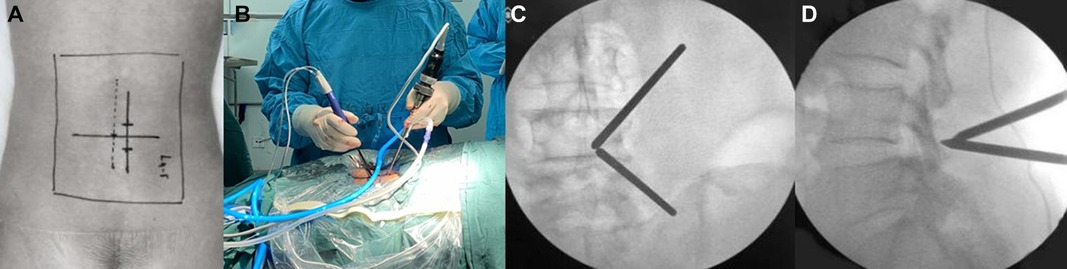

The surgery involves making a small cut—either in the front of the neck or the back—depending on the disc location. The part of the disc pressing on the nerve is removed.